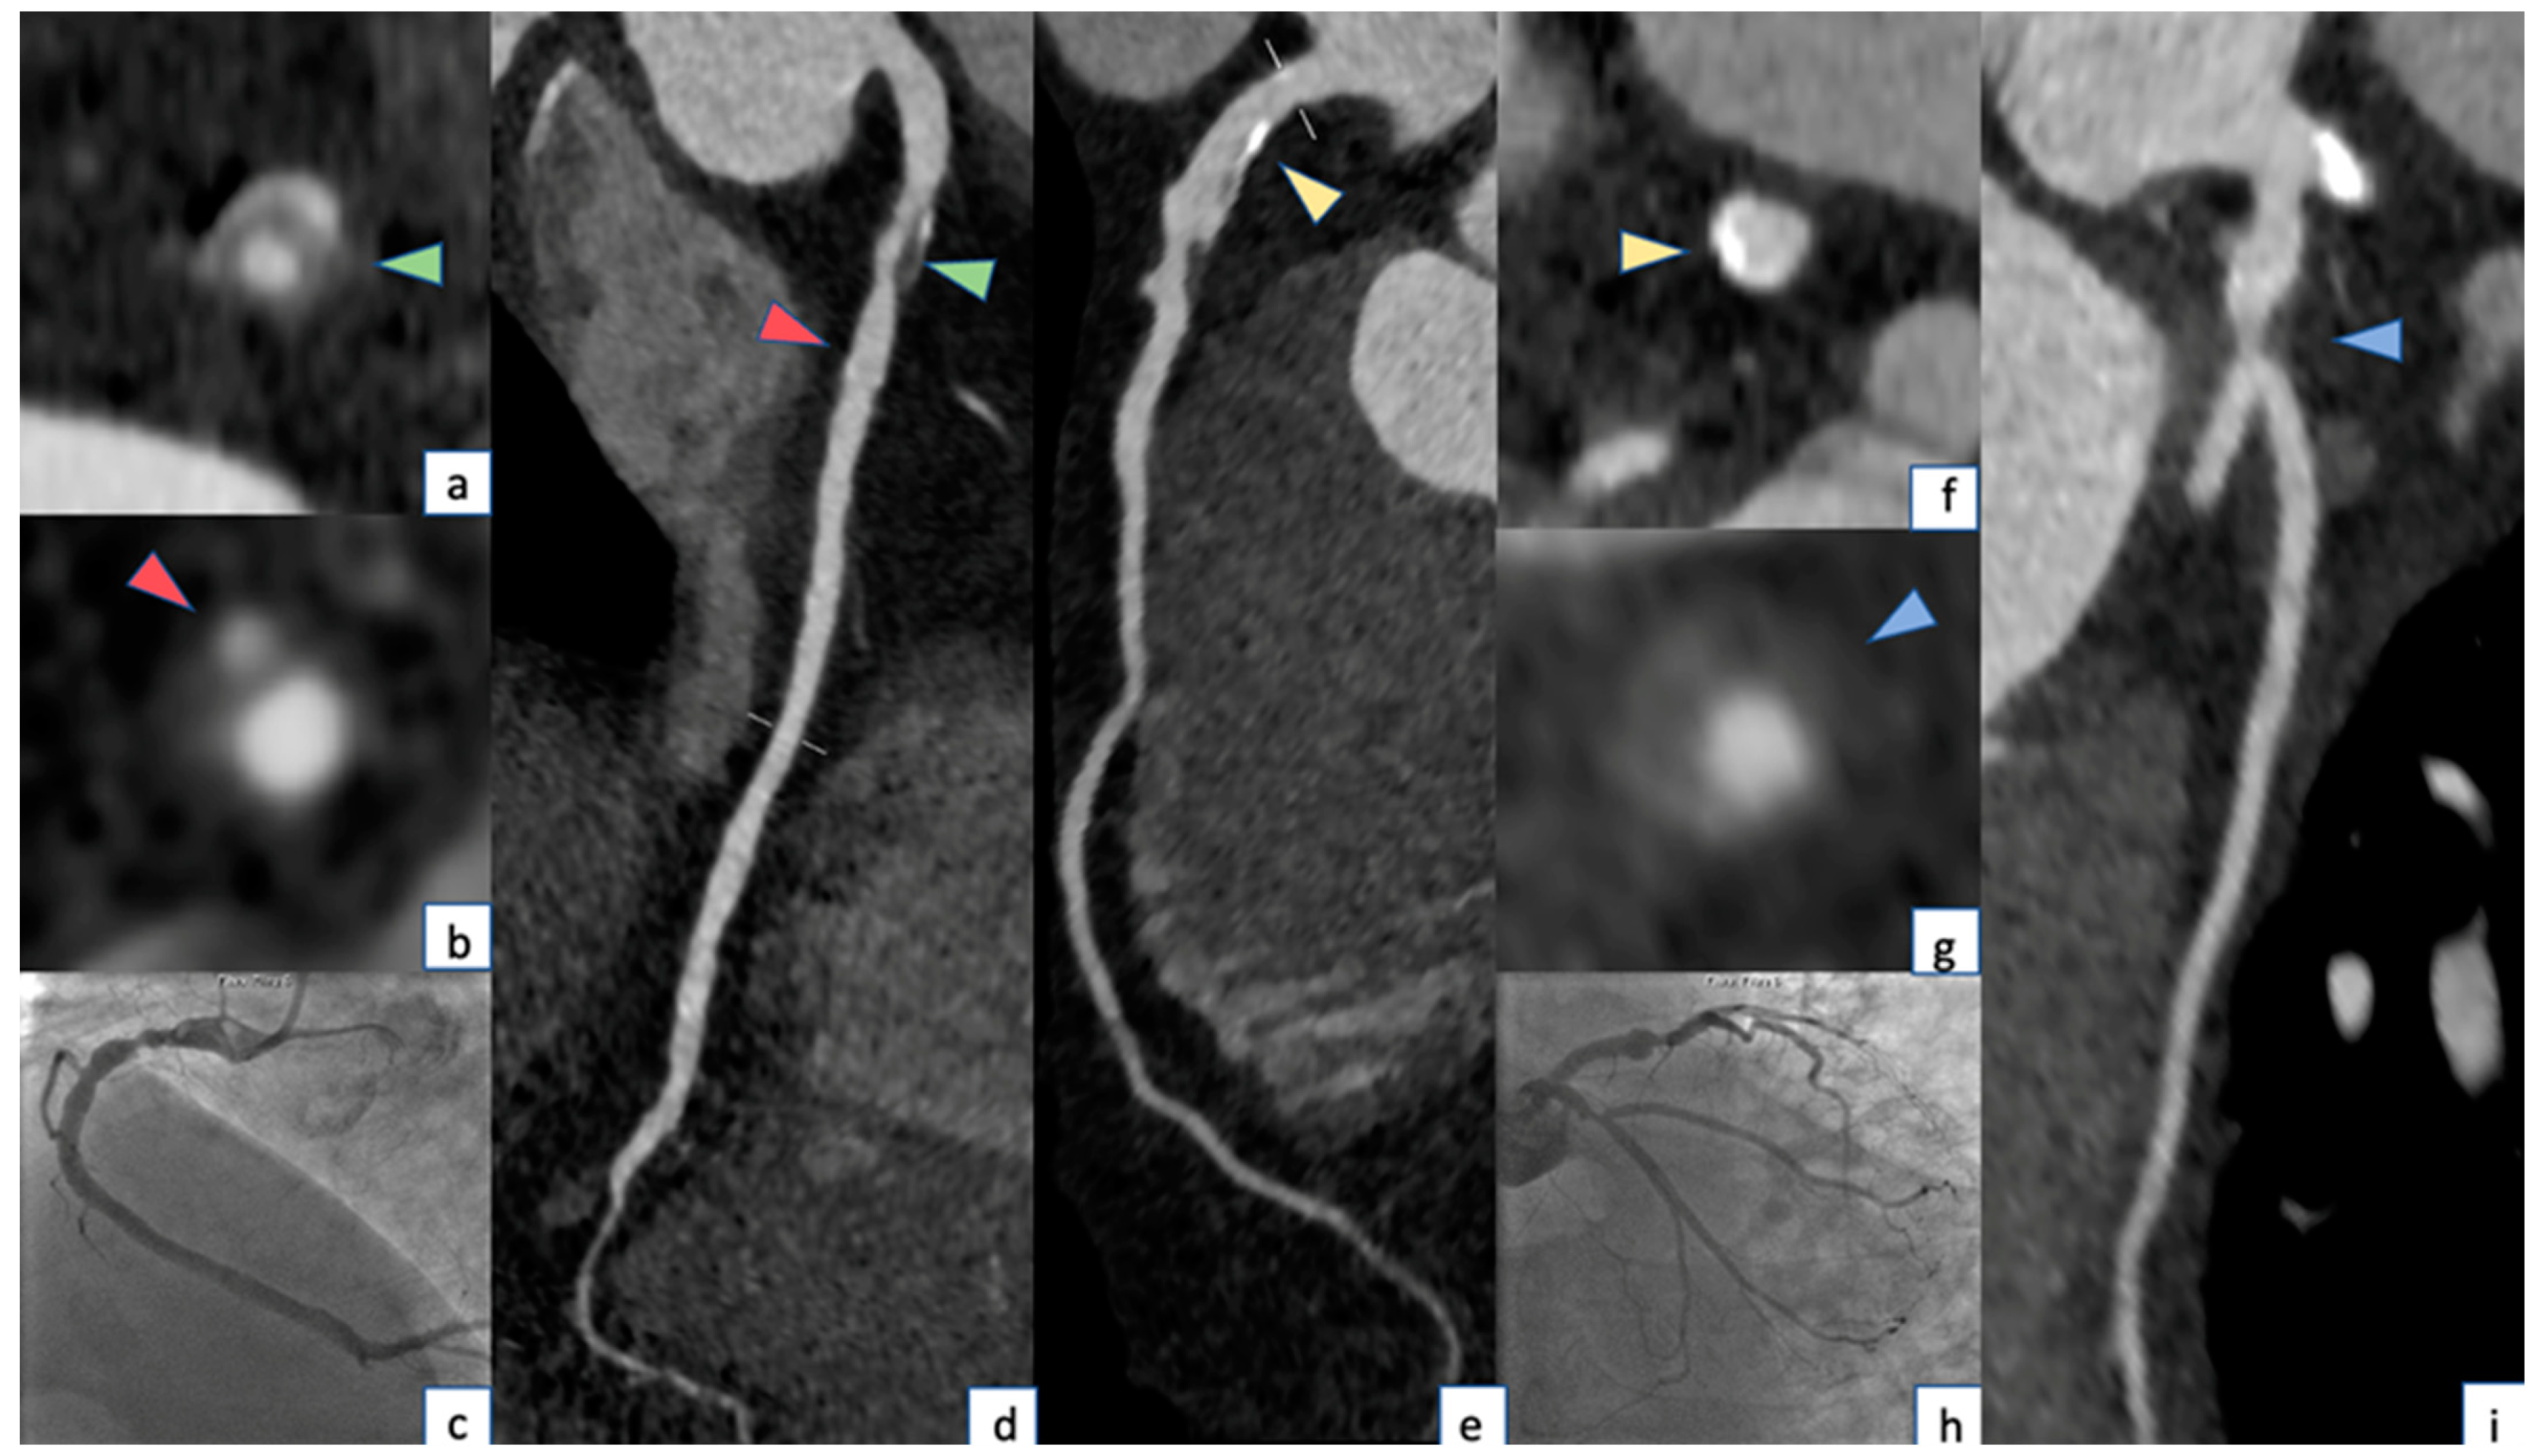

4.1. Retrospective ECG Gating

6.1. Low Attenuation

6.2. Positive Remodeling

6.3. Spotty Calcifications

6.4. Napkin-Ring Sign

6.5. Pericoronary Fat

6.6. Geometry of Coronary Plaques